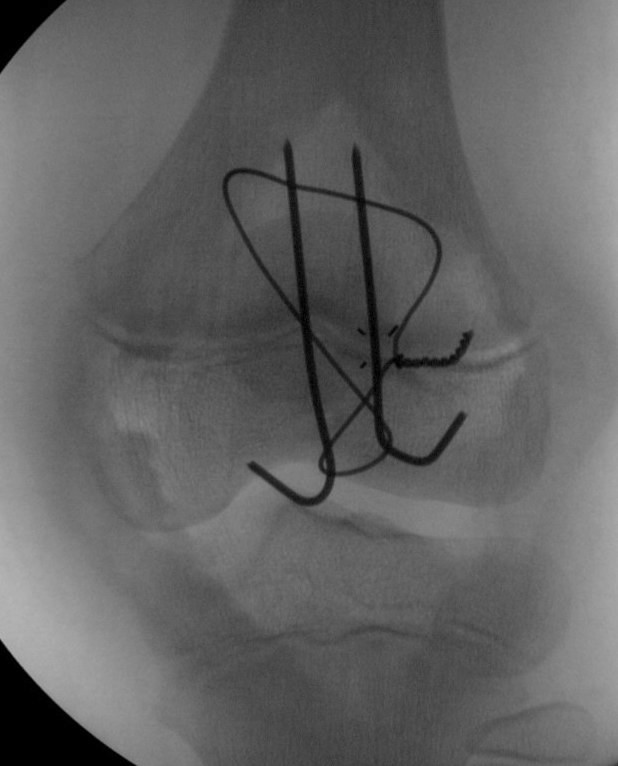

Displaced > 2 mm

ORIF

Technique

- intra-osseous sutures

- tension band wires

- suture anchors

Patella sleeve ORIF with tension band wires